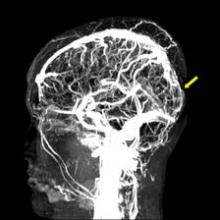

If a clinician suspects CVT, either MRI or magnetic resonance venography (MRV) is recommended to make the diagnosis by showing a thrombus obstructing the venous sinuses or cerebral veins. In emergency departments, either a CT scan or CT venography can be used if MRI is not available. "This allows different clinicians to initiate the appropriate work-up in the acute setting," Dr. Saposnik said.